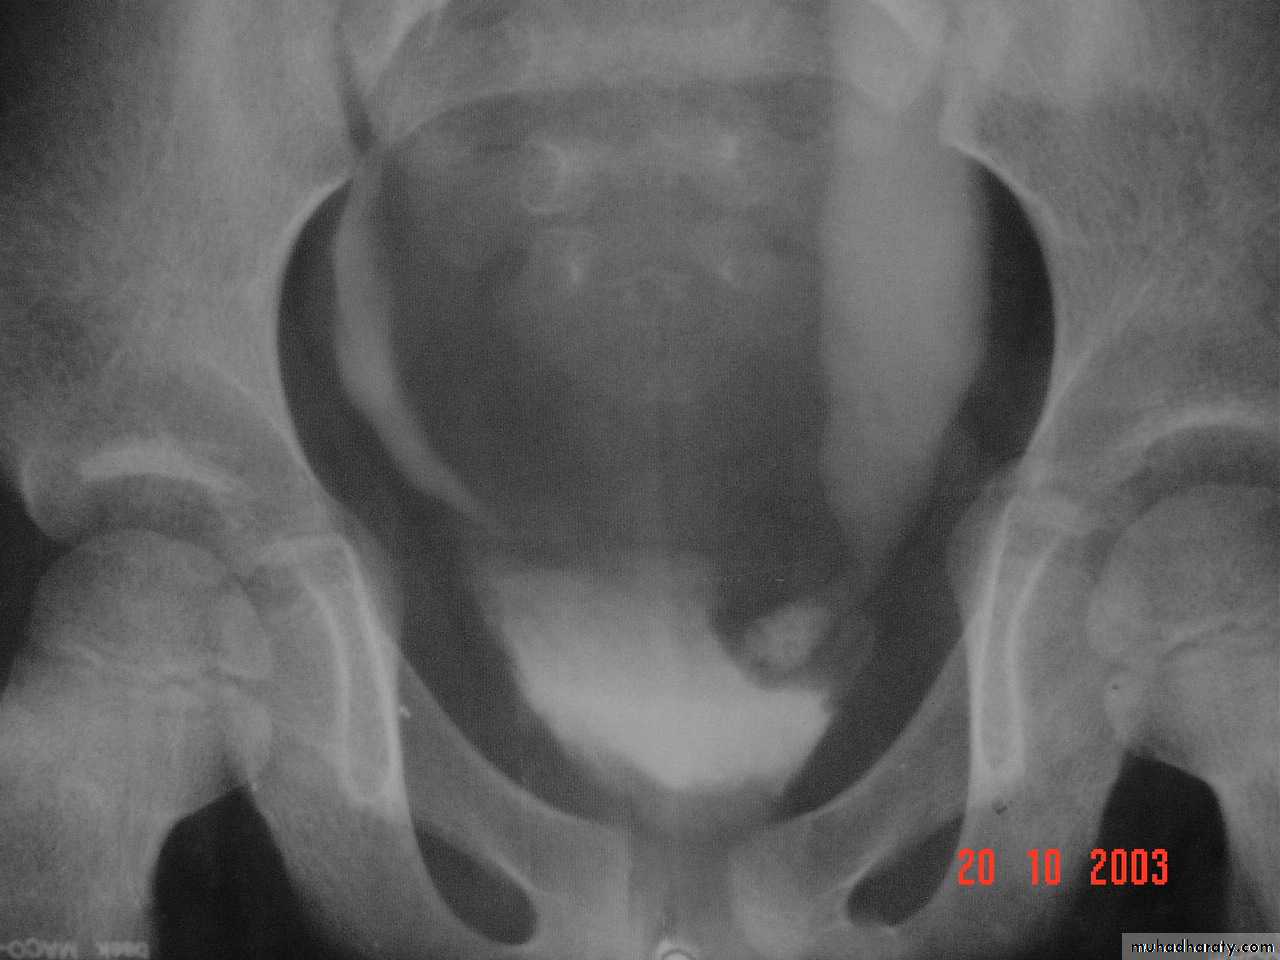

Ectopia vesica :

bladder located at low position & plain x-ray shows separation of symphysis pubis .